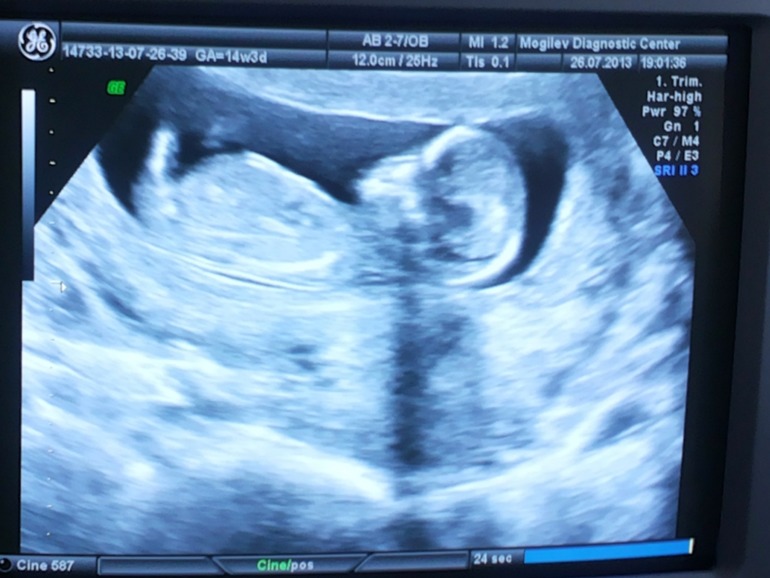

Вот оно - 6,5 см счастья... Самого большого в мире счаааааастья, но пока еще такого маленького!!!

Но немножко про само УЗИ...

В этот раз у меня стоял второй экран... И изображение было сильно увеличено (не то что в первую Б, где я даже толком ничего не смогла рассмотреть). И я не моргая смотрела на своё ПРЫГАЮЩЕЕ СЧАСТЬЕ!!! Да-да, малышка всё время прыгала, так забавно подкидывая попу!!! Я прям сама чуть не запрыгала от такого зрелища!!!Я такого никогда в жизни не видела... Картинка эта останется на всю жизнь перед глазами... Жаль только, что наш папочка не смог присутствовать... Но зато сразу после УЗИ выбежала из кабинета и сразу же отправила фоточку папе нашему за сотни километров. Он был безмерно счастлив!!!

Ну а данных на бумаге совсем что-то мало: КТР - 65 мм, толщина воротникового пространства - 1,5 мм... Вот и всё... В основном, только одни плюсики, что структура органов ребеночка визуализирована. Пороки развития не выявлены и риск по синдрому Дауна совсем маленький.

А еще срок по месячным поставили 14 недель и 3 дня.

По УЗИ - 12 недель и 5 дней.

А по моим данным - 11 недель и 6 дней. Но я-то лучше знаю))) И хорошо помню тот день - день приезда нашего папочки после 2-недельной разлуки...

Ну а ПДР где-то в конце января-начале февраля.